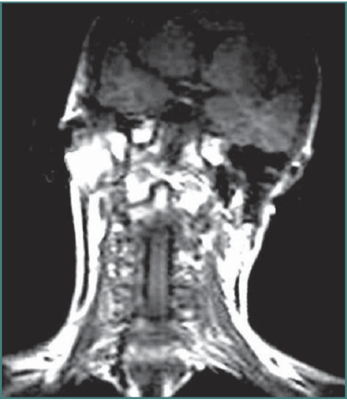

- Determination if neck or head or both are involved, description of abnormal posture and determination of muscles to be targeted.

- Determination of axis

GENERAL PRINCIPLES- CO-CONTRACTION

Voluntary movement is affected by co-contracting muscle pairs. It is important to assess range of individual neck movements but also the effort required and the localisation of pain associated with the movement.

In this patient there is co-contraction of ipsilateral Trapezius and Levator scapulae on the left, restricting rotation to the left and causing local pain